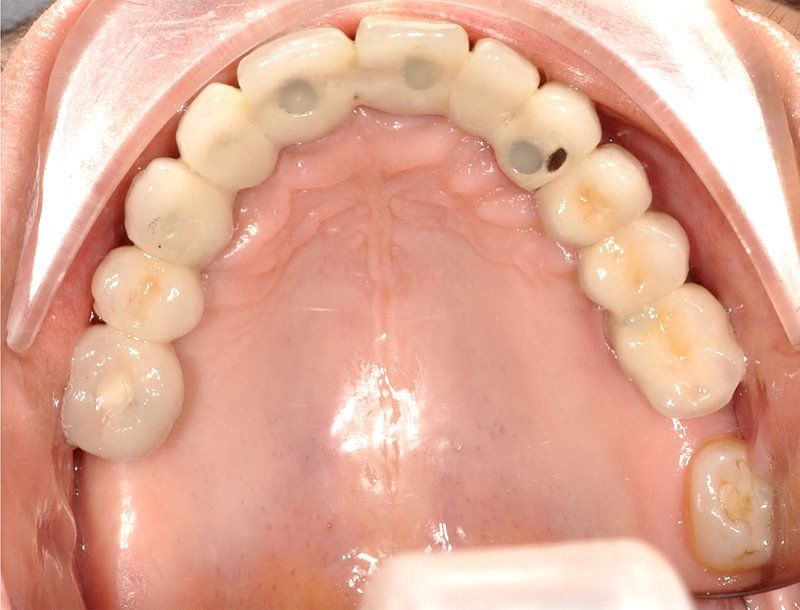

Los Implantes de Carga Inmediata son una solución práctica y definitiva para el desdentado total, es un tratamiento el cual una vez que se opera y se colocan los implantes, por un periodo entre 24 horas a 48 horas, se colocan los dientes en forma provisional, de esta forma el paciente queda con algo fijo mientras el implante se adhiere al hueso. Su principal ventaja radica en la reducción o eliminación del tiempo de espera entre la colocación del implante dental y la colocación de los dientes fijos.

Son recomendables para personas que no están dispuestas a una prótesis removible y quienes quieren acortar los tiempos de espera.